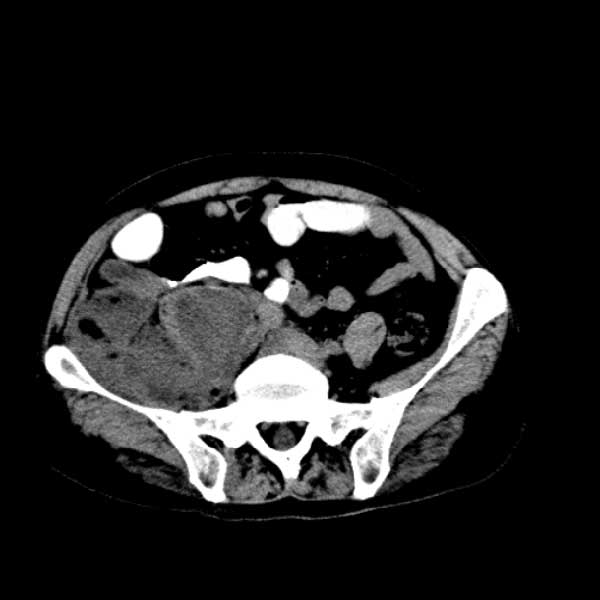

标题: CT13513:男 71 腹部疼痛20余天,近几天高热就诊,骨窗未见异 [打印本页]

考虑右侧腰大肌脓肿,向右髂窝、右腹股沟流注。

支持化脓性阑尾炎伴右髂窝脓肿、腰大肌腰方肌脓肿形成。

考虑腹腔及盆腔化脓性炎症,累及右侧髋关节及腹股沟区.

首先考虑化脓性阑尾炎伴腰大肌、腰方肌脓肿,不除外回盲部结核。

回盲部癌待排除。

患者肠镜检查考虑结肠癌,病理证实

患者肠镜检查考虑结肠癌,病理证实。肺部ct可见多发结节,考虑转移